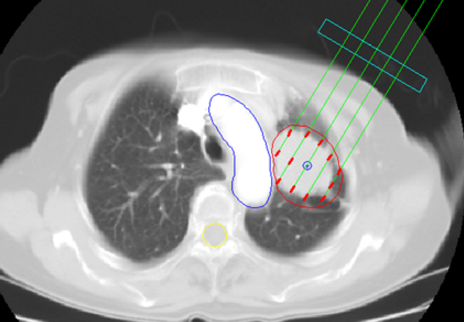

2.X線表現(xiàn)

多數(shù)于停止放療一月后,肺部出陰影。放射性肺炎急性期在照射的肺野上出現(xiàn)彌溫性片狀模糊陰影,其間隱約可見網(wǎng)狀影,酷似支氣管肺炎或肺水腫。

病變的范圍與胸廓表面照射野一致。慢性發(fā)生肺纖維化,呈條索狀或團塊狀收縮或局限性肺不張。